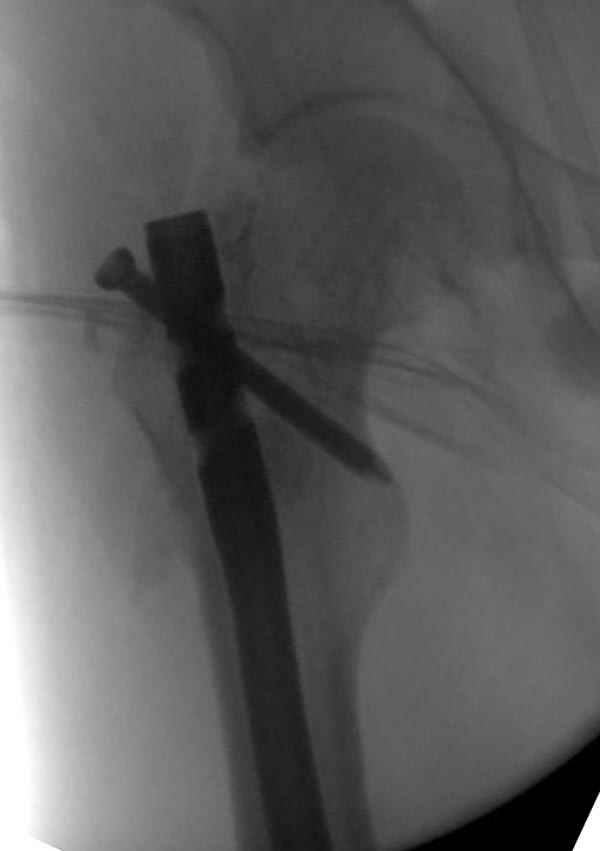

если первые 4 месяца послеоперационного периода проходил без проблем, но на 5 месяце появились боли в дистальном отделе бедра и температура, т.е. симптомы медуллярного инфицирования (рис №3, №4).

Замена реконструктивного штифта “Custom made Nail” с антибиотиком (рис №5, №6),

после промывки канала с рассверливанием внутреннего кортекса, через 4 недели антибиотический штифт удалили, оспалителный процесс остановлен и бедро сросся.